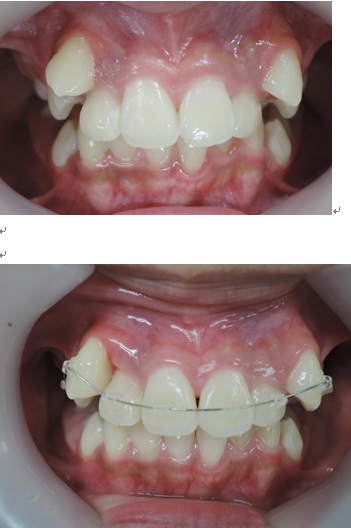

よく診る、難しい症例(奥歯の隙間)

歯列不正

歯を抜かないと治療出来ないと言われた方に。(歯並びが悪い)